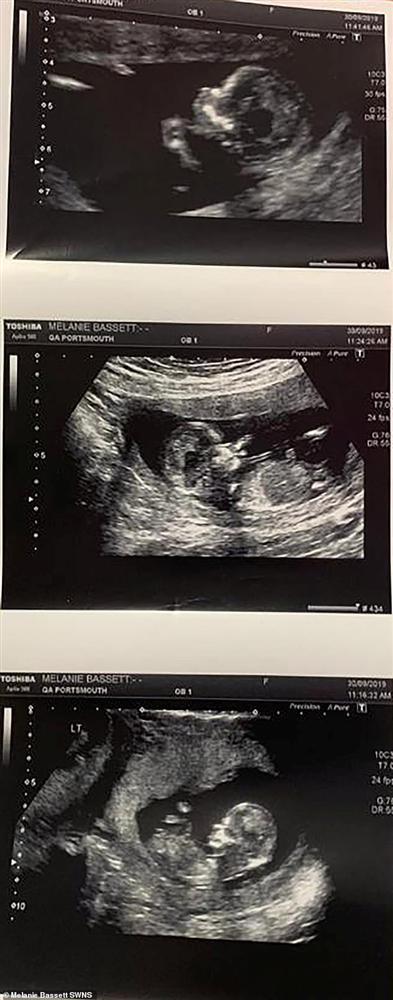

Song, chỉ hai tháng sau khi sinh Blake, chị Melanie phát hiện mình có thai lần thứ 3. Lúc siêu âm ở tuần thứ 8, bà mẹ được thông báo là có 2 nhịp tim. Nhưng đến tuần thứ 12, vợ chồng chị Melanie sửng sốt khi nghe bác sĩ báo họ sắp sửa chào đón 3 em bé, trong đó có 1 cặp song sinh.

Từ đó, chị Melanie phải đi siêu âm hai tuần một lần để bác sĩ theo dõi chặt chẽ, vì họ lo ngại rằng em bé có khả năng sẽ bị mắc hội chứng truyền máu song thai – một tình trạng khiến lưu lượng máu từ nhau thai phân bổ đến hai em bé không đồng đều